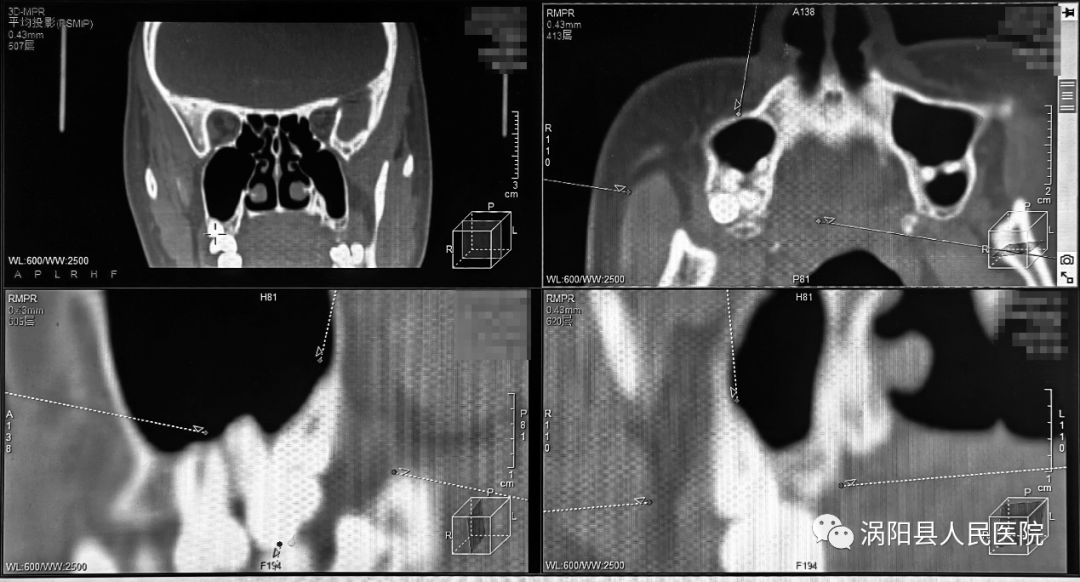

患者术前影像资料,可见上颌双侧第三磨牙埋伏阻生且位置较深、属超低位阻生,距离上颌窦较近。